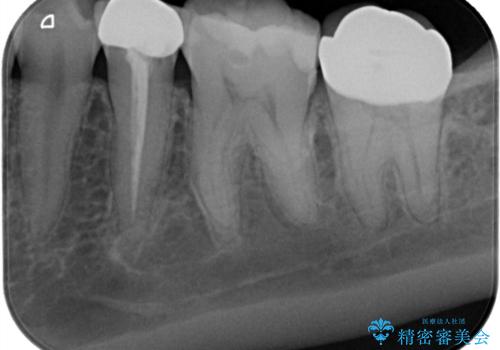

- 奥歯に虫歯があると言われて治療された患者様です。

何度か同じ歯に保険治療で治したそうですが、欠けたり再度う蝕になってしまった経験から自費治療を希望され、丈夫でキレイなセラミッククラウンにて治療いたしました。